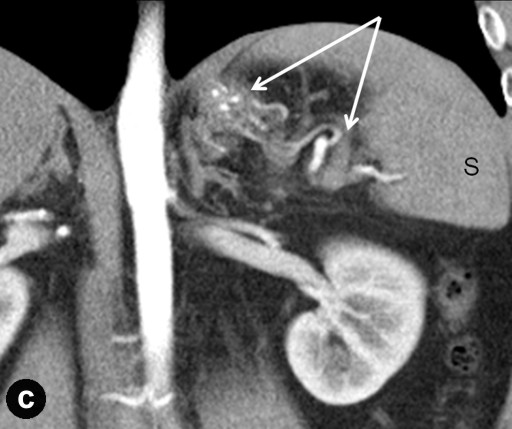

CT Angiography

Preceding surgery, the splenic artery was always seen on CT angiography as a thick stem with no other branches travelling to the spleen (Figures 7a and 8a). As a consequence of splenic artery resection, the whole or the bulk of its trunk were no longer available for evaluation by CT angiography after a spleen-preserving distal pancreatectomy with resection of the splenic vessels and, in all 10 cases, the gastroepiploic arcade was seen to have become the “highway” to the spleen within 7-30 days after surgery (Figures 7b, 8b, and 9). In two cases, due to technical reasons, 3D CT angiography was only carried out postoperatively but, in both cases, there were no doubts about the source of the blood supply to the spleen (Figure 9). In none of the 10 cases was any appreciable blood flow through the short gastric arteries visualized.

Thus, 3D CT angiography after a spleen-preserving distal pancreatectomy with resection of the splenic vessels did not reveal any reliable blood flow via the short gastric arteries. In all cases, the dominant role of the left gastroepiploic artery serving as the main blood supply to the spleen through the gastroepiploic arcade was observed.

Figure 8. Celiaco-mesenterial anatomy in а 59-year-old woman with a neuroendocrine tumor of the pancreatic body and tail. 3D CT angiography after the renal artery images were eliminated. a. Before surgery: the splenic artery thick trunk with no collaterals is shown. b. Ten days after a spleen-sparing distal pancreatectomy with resection of the splenic vessels: the spleen is fed through the gastroepiploic arcade. There are no other detectable major arteries to feed the spleen. c. After surgery, vertical view: the arrow is pointing to the gastroduodenal artery, i.e., the site of origin of the gastroepiploic arcade. GEA: gastroepiploic arcade; LGEA: left gastroepiploic artery; SA: splenic artery |